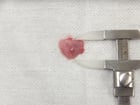

尿道に結石がつまり、尿が出なくなった犬。こうなると、膀胱破裂あるいは腎不全を起こして死亡する可能性が高い。結石を取り除き尿道カテーテルを挿入する緊急手術を行った。右写真は摘出した5mm大の結石。